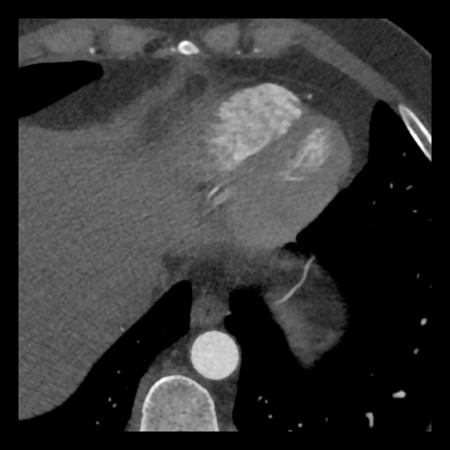

Same patient. First, study the CTA image.

How would you describe the findings?

The coronal image shows a central low-attenuation area around the lumen

of the LAD.

This low-attenuation area is surrounded by a higher attenuation

area.

This finding is the earlier discussed napkin-ring sign, which is a high-risk

plaque feature.

This patient classifies as CAD-RADS 4A/P1/HRP.